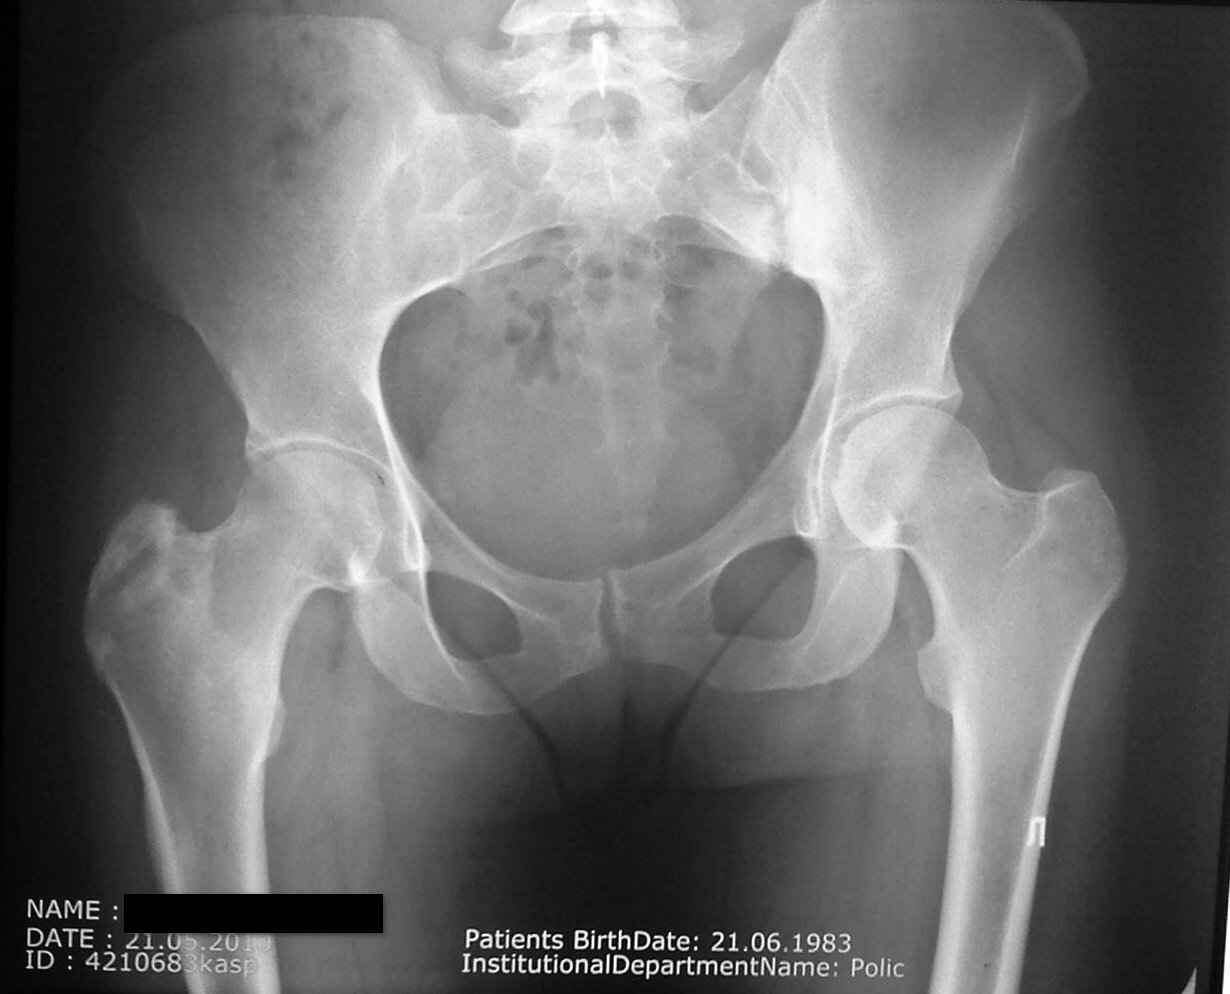

Я пологаю пациентку беспокоит левый т/б сустав? Скорее всего это связано с деформацией таза ( перекос ), в следствии укорочения капсульно-связачного аппарата, ограничение движений. Мануальная терапия, массаж, ЛФК, ФТЛ.

Похоже на Бехтерева, нужно КТ и ревмопробы, может быть скандинавский тип.

Так все таки какой сустав? На Бехтерева не очень похоже, ревмапробы можно сдать.

Пациентку беспокоит правый тазобедренный сустав в области вертела (именно там где имеются рентгенологические проявления . Сегодня мне были доставлены выполненное ей ранее РКТ правого коленного сустава(имеются выраженные изменения (лизис мыщелка бедра и дополнительное образование в межмыщелковом возвышении) . В биохимических анализах по ревматоидной программе изменений нет. В ОАК повышена СОЭ (29).

а мне кажется что есть изменения в большом трохантере правого бедра , смешанного характера(лизис склероз) стерты границы латерального кортекса и мягкие ткани не так четко видны как справа .. МРТ , костное сканирование , если что то есть - костная биопсия с бактериологическим исследованием ...

В верхней части диафиза выраженная периостальная реакция, над черной полосой закрывающей имя пациентки. Наверное туберкулез. Нужна биопсия и посев.

Уважаемый Олег! У больной, вероятней всего, имеется туберкулезный трохантерит справа (незначительные боли, ограничение функции тазобедренного сустава, на Р-грамме - остеопороз!!!, деструкция б.вертела, уплотнение мягких тканей. Больной показана операция - некрэктомия очага деструкции и пластика аутокостью. Бак. и гистологическое исследование операционного материала верифицирует патологический процесс. Кстати, замечу ответственно уважаемому ортопедическому сообществу, положительные результаты посева на микобактерию туберкулеза при активных процессах составляют всего 20-25%, так что отрицательный посев не означает исключение туберкулезного процесса! Желаю успехов!

Такое ощущение, что имеется анкилоз в правом крестцово-подвздошном сочленении справа. Может в какой-то степени и это причина боли!